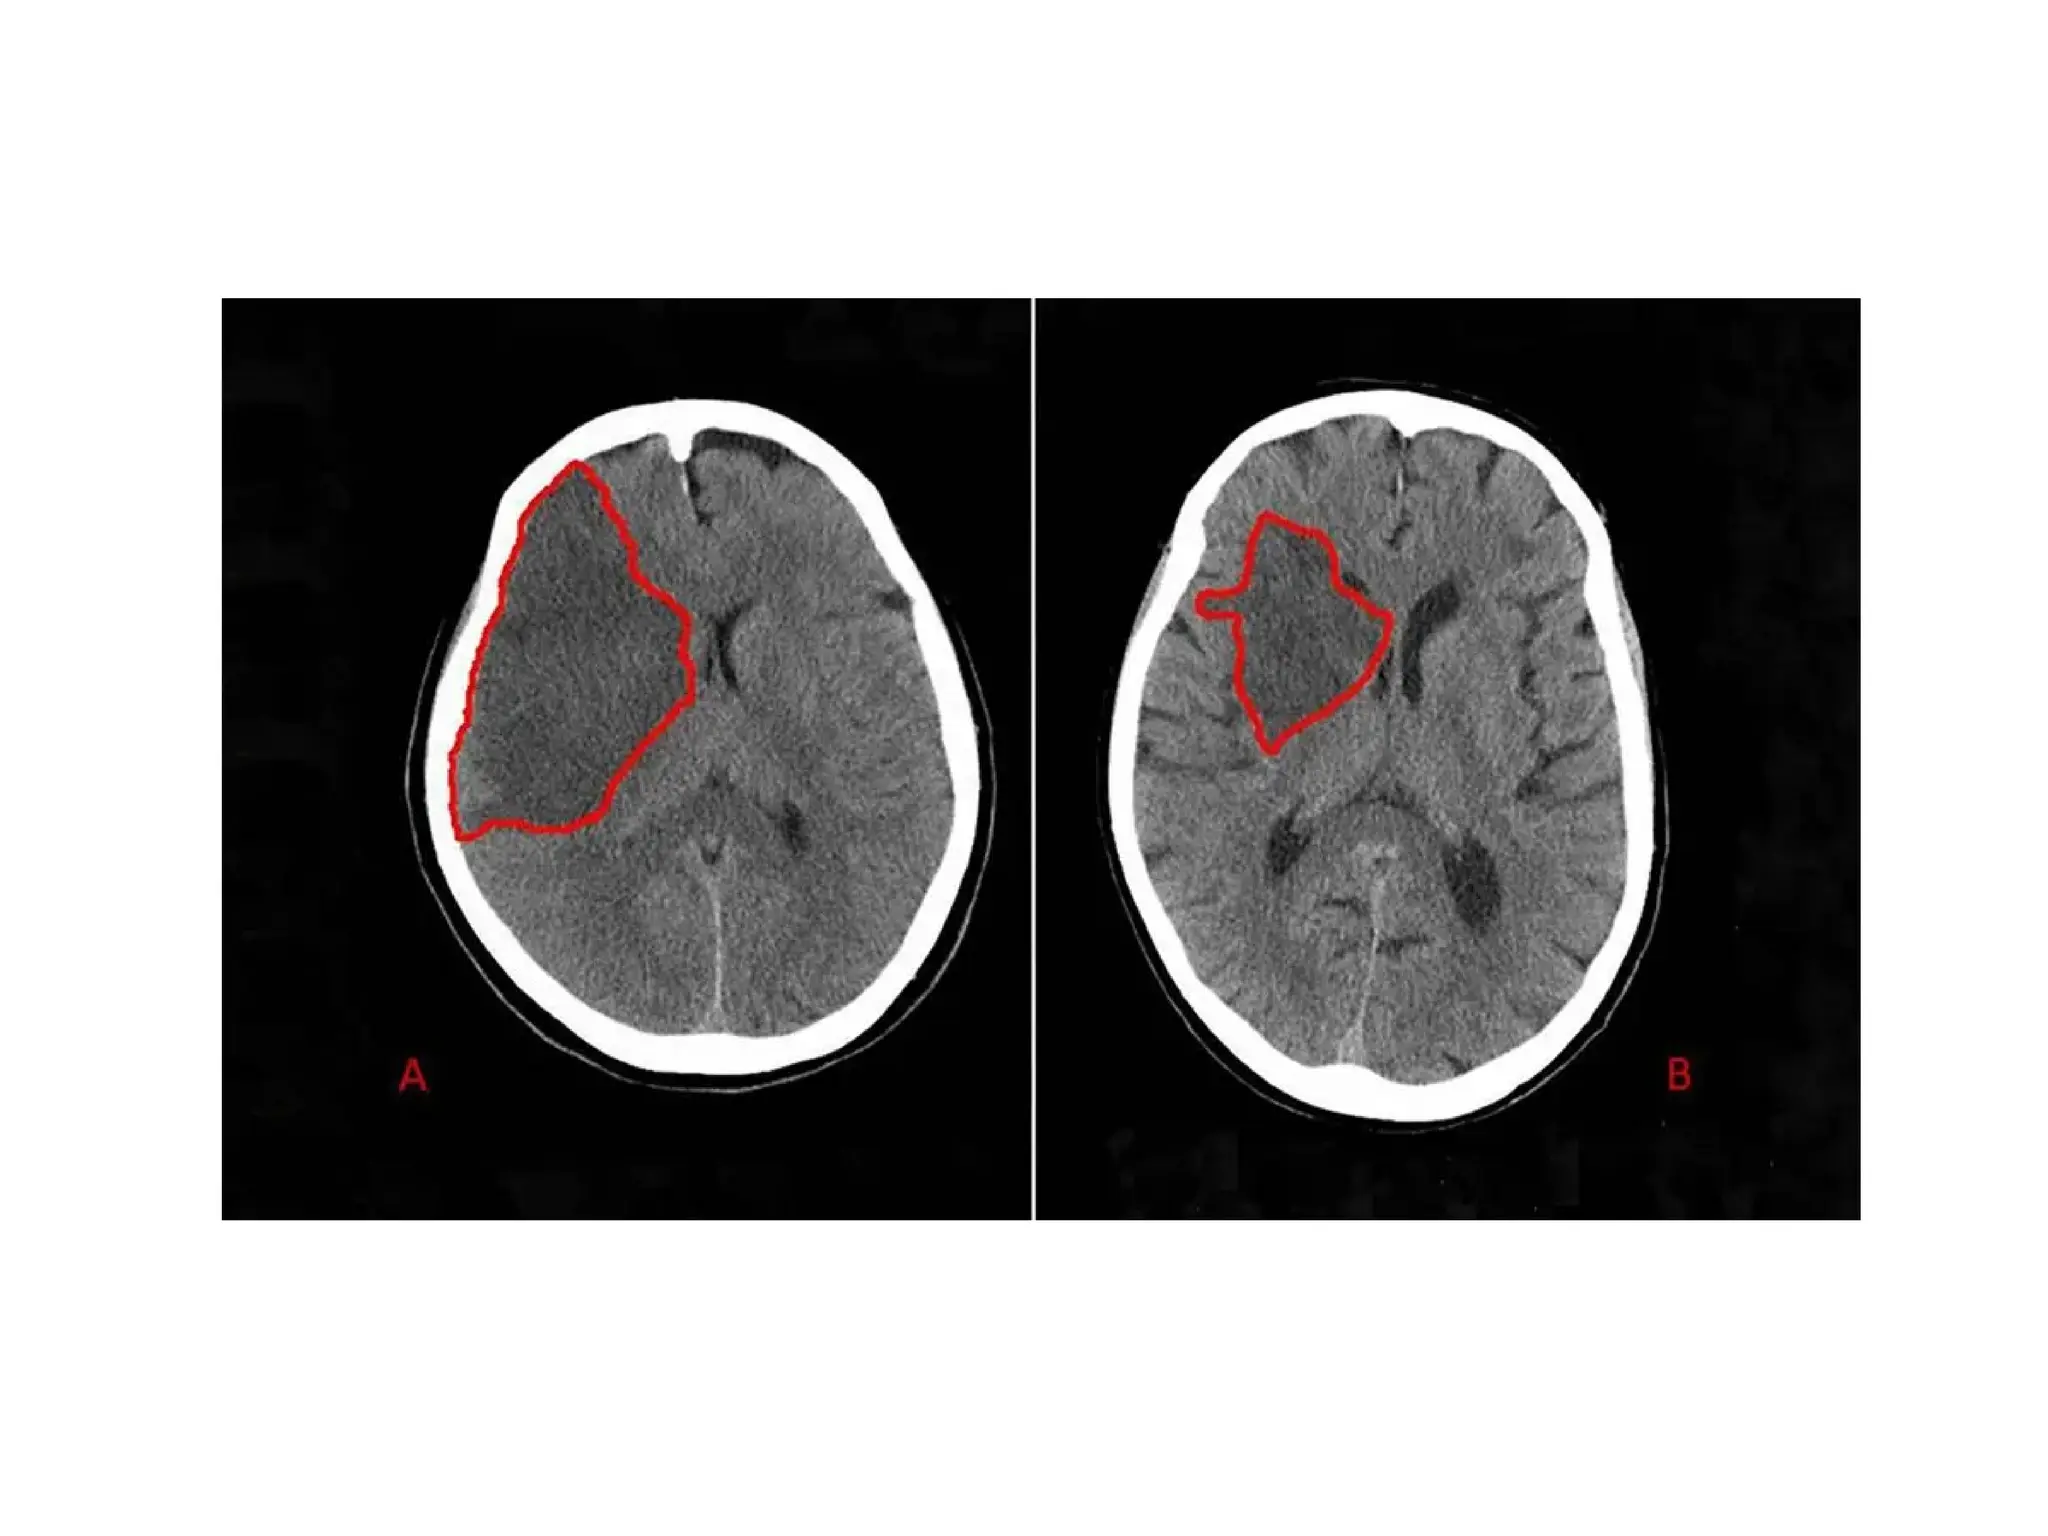

Hemorrhagic Stroke

Hemorrhagic Stroke

15% of all strokes

Result from bleeding into the brain tissue

itself

Intracerebral

Subarachnoid

Hemorrhage Stroke

Intracerebral Hemorrhage

Rupture of a vessel

Hypertension – most important cause

Others: vascular malformations, coagulation disorders,

anticoagulation, trauma, brain tumor, ruptured

aneurysms

Sudden onset of symptoms with progression

Neurological deficits, headache, nausea, vomiting,

decreased LOC, and hypertension

Prognosis: poor – 50% die within weeks

20% functionally independent at 6 months